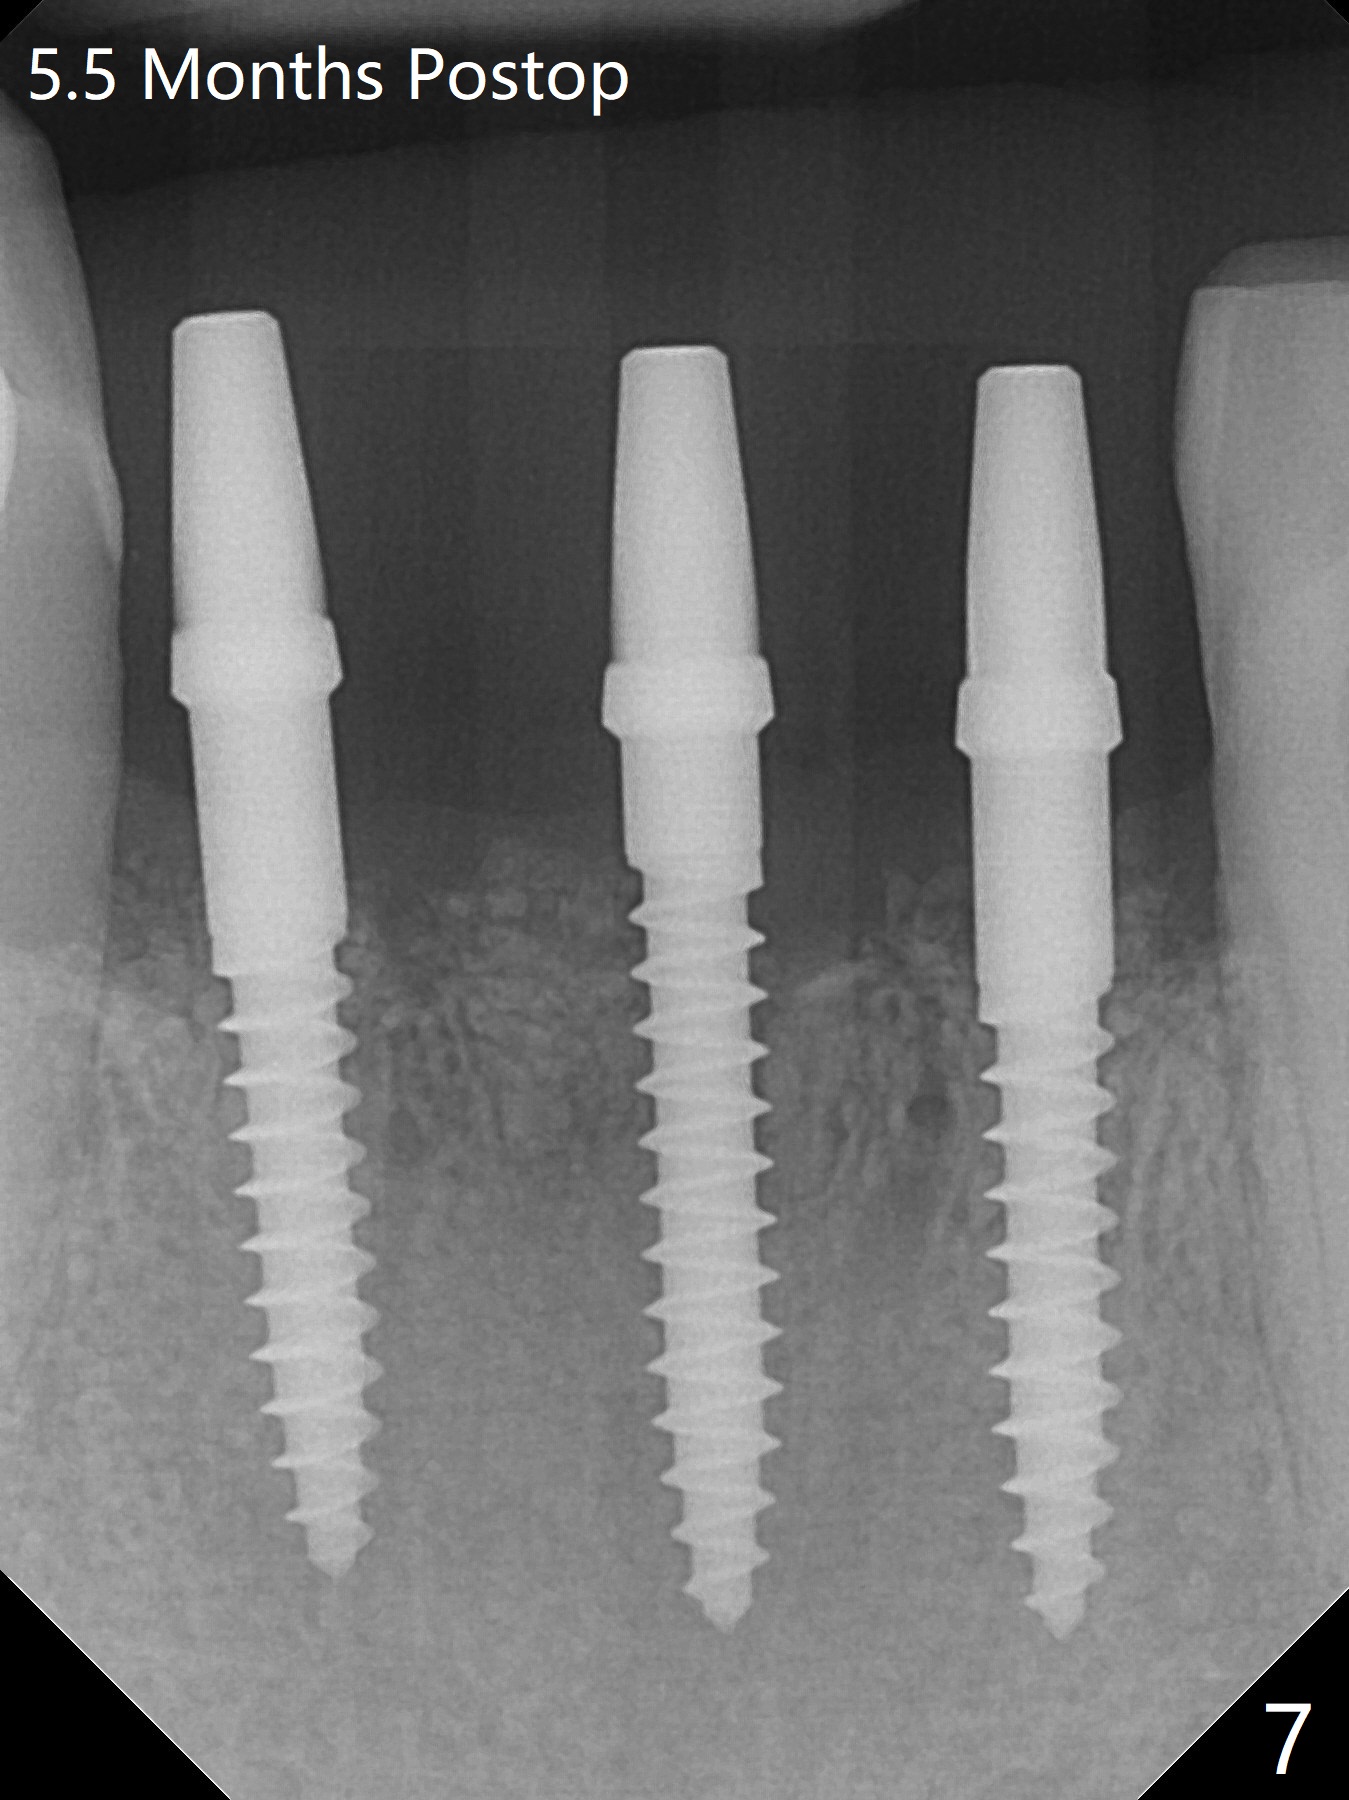

3 Implants for 4 Lower Incisors

When the patient returns, the tooth #24 has exfoliated, while the ones at #25 and 26 has mobility III (Fig.1). The patient requests the tooth #23 extraction (Fig.2), but not #27. After SRP and extraction, osteotomy is initiated mesial to the sockets #23,25 and 26 (Fig.3,4) with intention to place 3 1-piece implants for 3 incisor crowns (Fig.5,6). Following Vanilla graft (Fig.5 *) a splinted provisional is fabricated to close the sockets (Fig.6). Peri-implant spaces close 5.5 months postop (Fig.7). Impression is taken after reprep for margin and parallelism (Fig.8). The final restoration consists of #23 single unit crown and #24-26 3-unit FPD (Fig.9). It appears that 2.5 mm 1-piece implants are not too small for the lower incisors (Fig.10-12), especially the central one (Fig.11). There may be perforation in the apical half of the lingual plate (L in Fig.10). The patient is not pleased with the shade of the #24-26 3-unit FPD (Fig.13 (6 months post cementation)). There is metal show through the abutments (*).